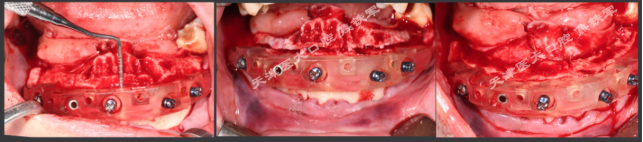

下颌即刻种植即刻修复手术过程

· 下颌士卓曼360数字化序列导板+预成临时修复体

· 翻瓣,利用松牙固定后的余留牙支持连接在一起的牙支持导板和基部导板,使骨支持的基部导板就位于骨面。

· 并用固位钉固定,拆除牙支持式导板,拔除余留牙。

· 基部导板上缘做为截骨线,精确去骨,平整骨面。

· 全程植入导板就位于基部导板上,固位钉固定,引导种植体植入。

· 种植体植入后,安装复合基台基底

· 临时修复体就位于基部导板,固位钉固定,口内Pick-up后取下修改,戴回口内,咬合关系良好。